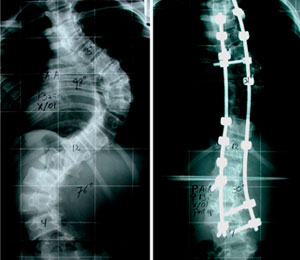

Después de mi operación, solo estuve internada 4 días. Tengo 11 tornillos en mi columna y ya llevo 5 años de operada; vivo una vida normal y soy feliz.